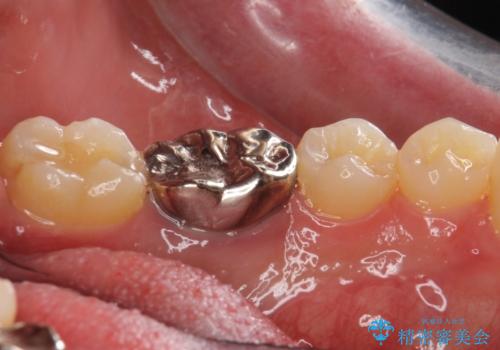

- 他の歯を治療中にレントゲン写真を撮ったところ虫歯を発見。

どうせなら1つ奥の銀歯も白くしたいとのご希望があり、2本ともセラミックにて治療をしていくことになりました。

虫歯治療に加え、奥の銀歯も同時にやり替えました。

精度の良いクラウンにやりかえることは今後の虫歯リスクを減らすことにつながります。